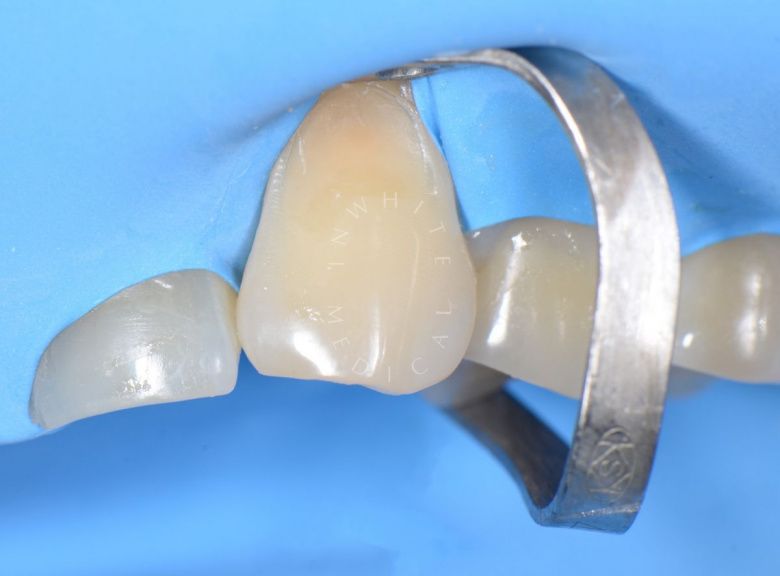

Лечение скрытого кариеса под старой пломбой

Лучшие стоматологические клиники. Лечение скрытого кариеса под старой пломбой  - до процедуры